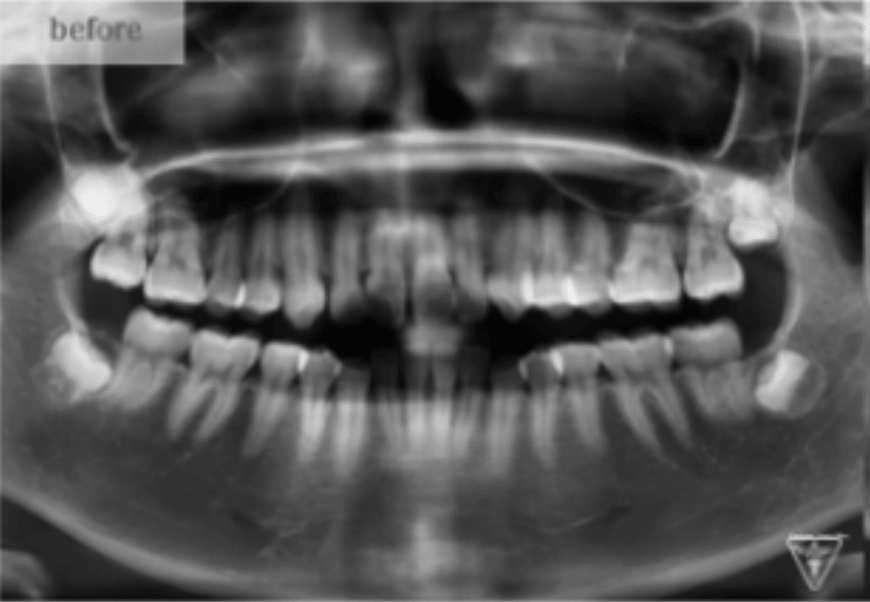

治療前

治療前後の比較